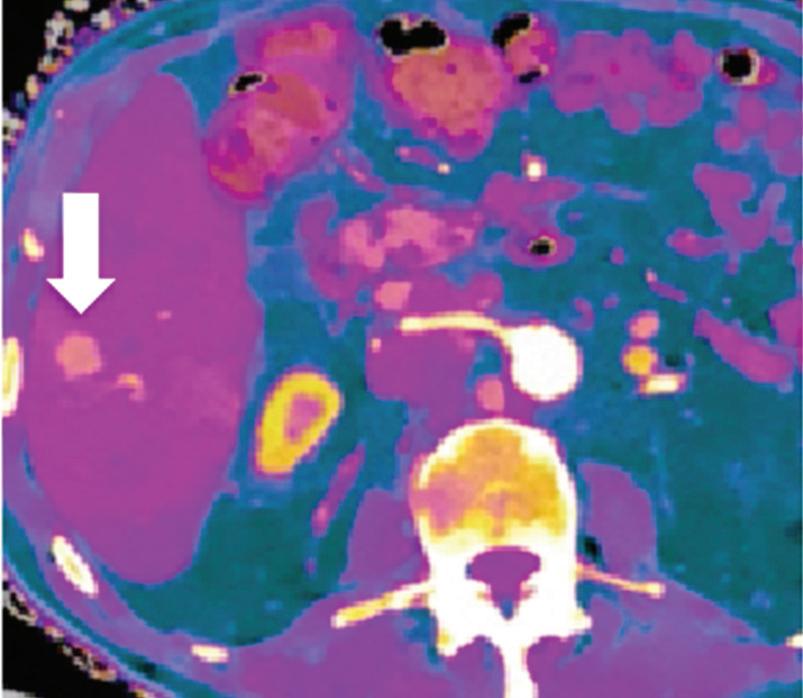

Renal and adrenal gland tumors. Contrast-enhanced-DECT images are particularly useful for the characterization of incidental renal or supra-renal lesions and for their follow-up, without the need of conventional unenhanced acquisition, translating into achieving a 30% mean dose savings for triphasic and up to 50% for biphasic renal protocols in daily clinical practice.17 It is also very useful in depicting hypervascular renal cell carcinoma metastasis in the liver or other sites, such as in the peritoneum and bowel wall (Figures 2 and 3).

Z effective

Spectral CT is able to generate Z effective images that show the mean atomic number of the material present in a voxel (Z effective values) and can be displayed as color coded overlay maps. Z effective images may be helpful to enhance the visual differences between different tissue types.46 Furthermore, due to the high atomic number of iodine compared to other tissues present in the human body, the Z effective images can highlight enhancing structures (Figures 2, 3, 4, and 5) and could be used for quantitative analysis to differentiate benign from malignant tumors or lymph nodes.16,45,47

Effectiveness of spectral CT imaging for detection of hypervascular liver metastases. A small hypervascular metastasis (arrow) from renal cell carcinoma. (a) Axial contrast-enhanced conventional CT image obtained in the arterial phase, corresponding (b) monoenergetic 50 keV, and (c) Z effective image.

Effectiveness of spectral CT imaging for detection of a peritoneal implant from a renal cell carcinoma invading the bowel wall (arrow). (a) Coronal contrast-enhanced conventional CT image obtained in the arterial phase, corresponding (b) Z effective, (c) monoenergetic 50 keV, and (d) iodine-density image.